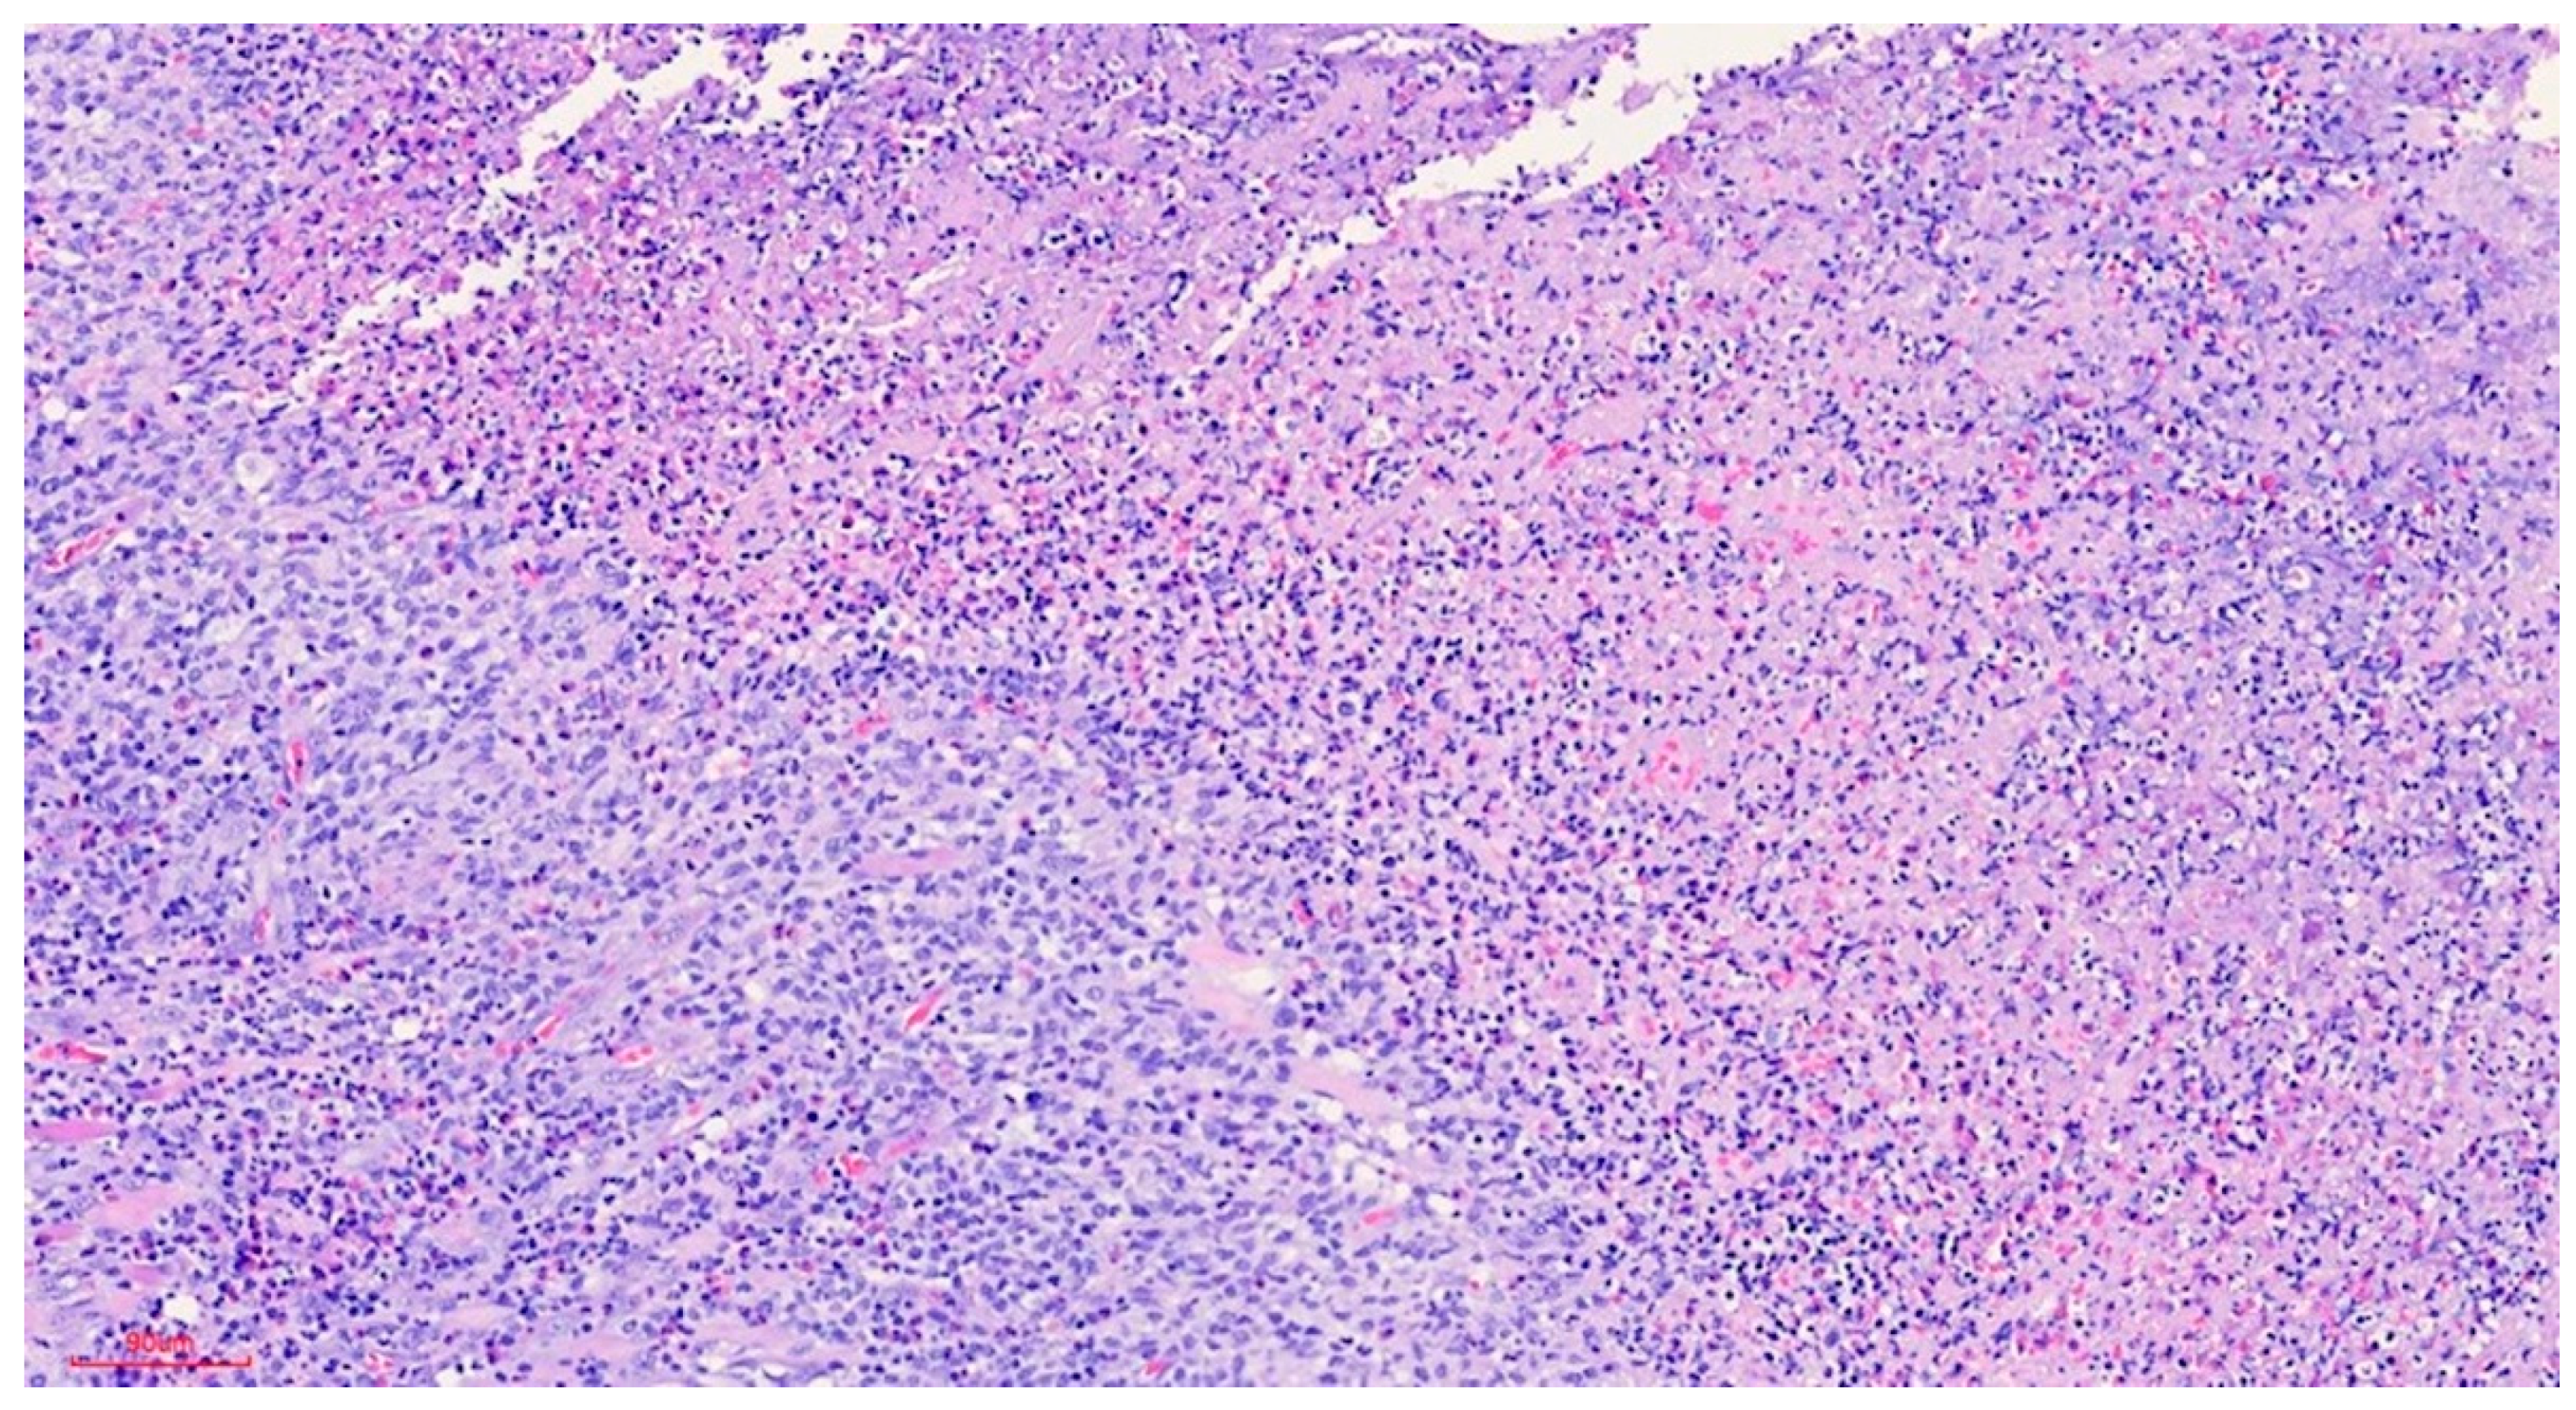

Clinically, the lesion usually has a raised hyperkeratotic border and microscopically it is characterised by a dense infiltrate of T and B lymphocytes, macrophages and mainly eosinophils24 and a tendency to penetrate the underlying muscle.

b) Microscopic findings: infiltrative ulcerative lesion covered with necrotic-fibrinoid material and consisting of an abundant polymorphous inflammatory infiltrate extending in depth around the seromucinous glands and dissociating the muscle fibres. It consists of cells of histiocytic type, lymphocytes, polynuclear neutrophils and abundant eosinophils. PAS and Grocott stains show no fungal elements. No signs of malignancy are observed (see Figures 4–9).

c) Histopathological diagnosis: histological aspect compatible with traumatic ulcerative granuloma with stromal eosinophilia.